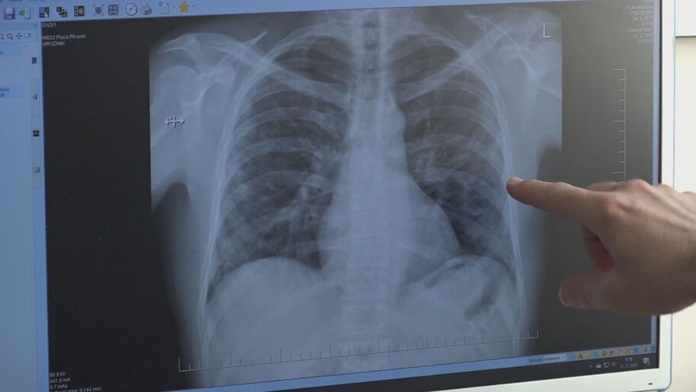

Ilustračná snímka. Zdroj: TV Markíza

Britke Dianne Coveyovej pomohol zachrániť život nástroj umelej inteligencie, ktorý odhalil nádor na jej pľúcach, píše BBC

Nástroj Annalise.ai využíva zdravotnícka organizácia Royal Surrey NHS Foundation Trust. Umelá inteligencia lekárom pomáha určiť, ktoré röntgenové snímky majú posúdiť ako prvé, čím sa mení zaužívaný prístup, pri ktorom sa snímky posudzovali v chronologickom poradí.

Lekárom nástroj zároveň pomáha aj v tom, že dokáže presnejšie odhaliť všetky drobné anomálie na snímkach.

Keď 69-ročná seniorka prišla lekárovi so silným kašľom, oznámili jej, že na pľúcach našli čosi podozrivé. Práve analýza nástrojom Annalise.ai potvrdila výskyt nádoru.